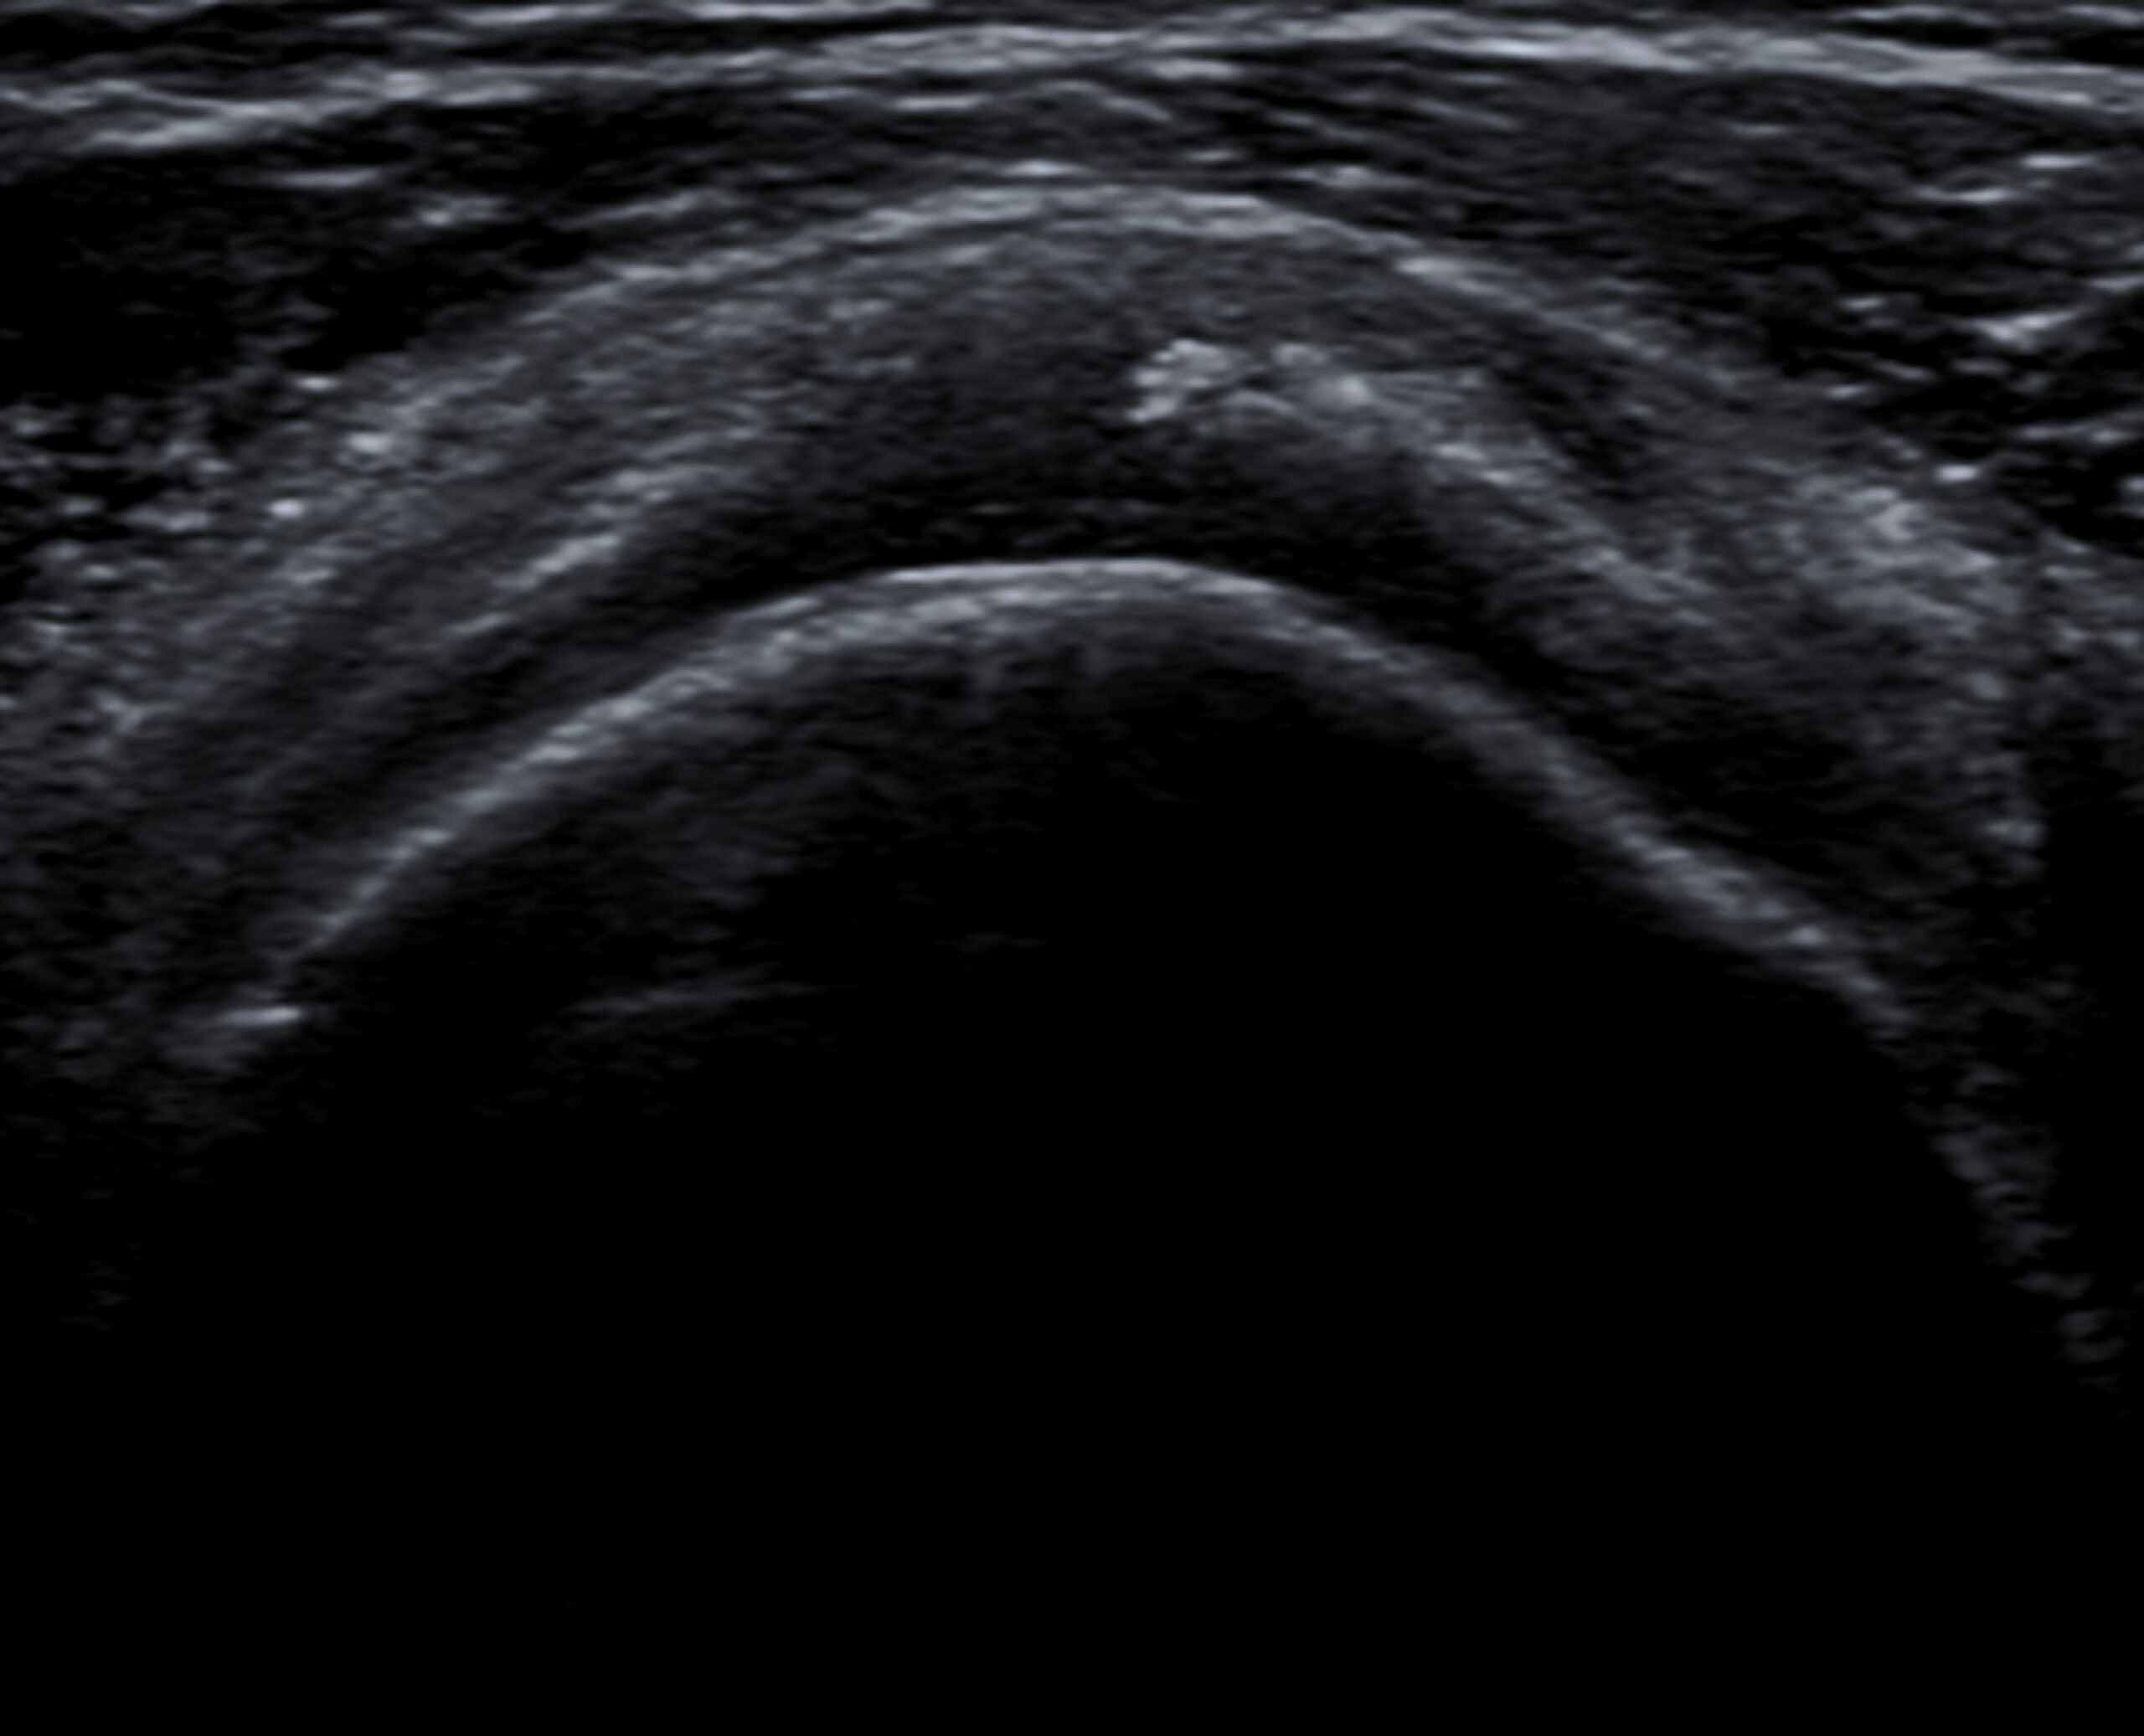

La ecografía juega un rol fundamental en el diagnóstico de la tendinopatía cálcica. Permite la caracterización de las calcificaciones, incluyendo la forma, tamaño y morfología. A diferencia de la radiografía, la ecografía tiene mejor correlación con las fases de la tendinopatía cálcica, y por ende mejor correlación con la sintomatología. En la fase de reposo, las calcificaciones presentan un arco ecogénico bien definido asociado a sombra acústica posterior, mientras que en la fase reabsortiva se presentan menos definidas, con morfología polimorfa, con sombra acústica parcial o ausente. En este caso, en eco se ve una imagen lineal ecogénica con sombra posterior (calcificación) en el tendón supraespinoso.

La técnica del lavado ecoguiado de las calcificaciones de hombro consiste en la colocación de una aguja bajo anestesia local en el centro de la calcificación, de tal forma que mediante la inyección a presión de suero salino o anestésico se rompa la calcificación y se vacíe el material cálcico a la jeringa utilizada para el lavado. En la eco y Rx de control se visualiza reducción significativa de la calcificación: